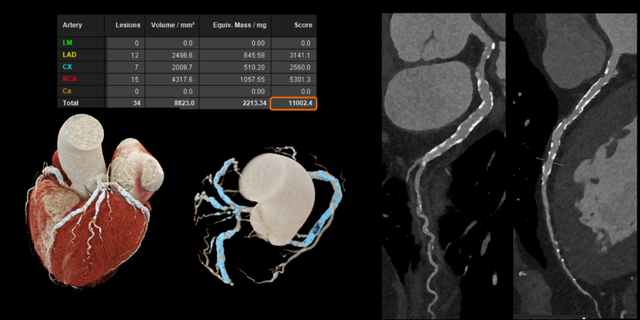

Với các bệnh tim mạch, đặc biệt ở những bệnh nhân đã đặt stent hoặc có mạch vành bị vôi hóa nặng - vốn là những trường hợp khó đánh giá bằng CT thông thường. Công nghệ này cho phép hình ảnh rõ ràng hơn đáng kể. Nhờ đó, bác sĩ có thể quan sát chính xác lòng mạch và các mảng xơ vữa, ngay cả khi bệnh nhân có nhịp tim cao hoặc loạn nhịp mà không cần sử dụng thêm thuốc hỗ trợ.

Hình ảnh mạch vành cho thấy độ rõ cao hơn, giảm nhiễu và giúp đánh giá chính xác hơn (Nguồn: Siemens Healthineers)